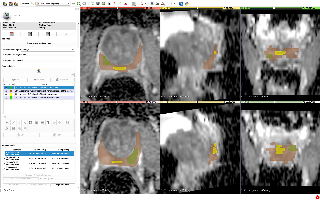

Verse大规模脊椎分割数据集

| VerSe | 脊椎 | 分割 | CC BY-SA 4.0 |